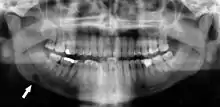

A basic panoramic radiograph